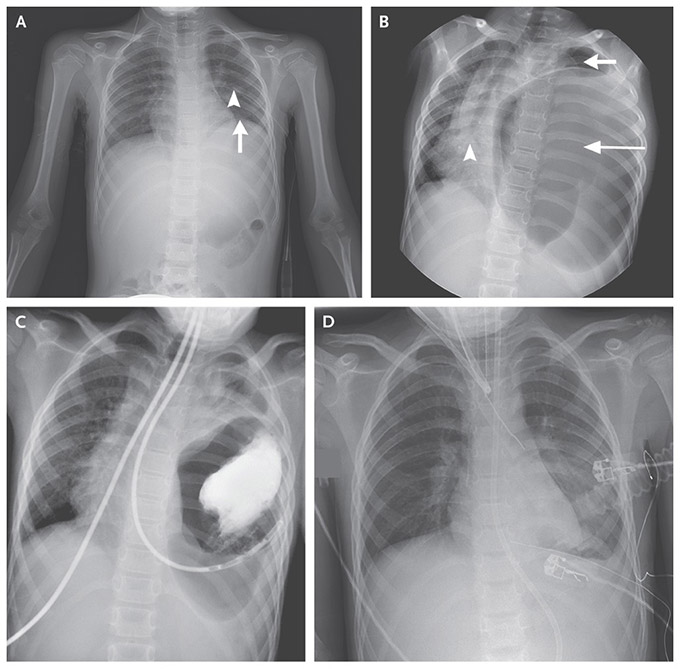

O diagnóstico da Hérnia Diafragmática Congênita e Traumática é feito por meio da realização de exames de imagem, como a radiografia, a tomografia computadorizada ou a ressonância magnética, que podem evidenciar a presença indevida de órgãos da cavidade abdominal dentro do tórax.